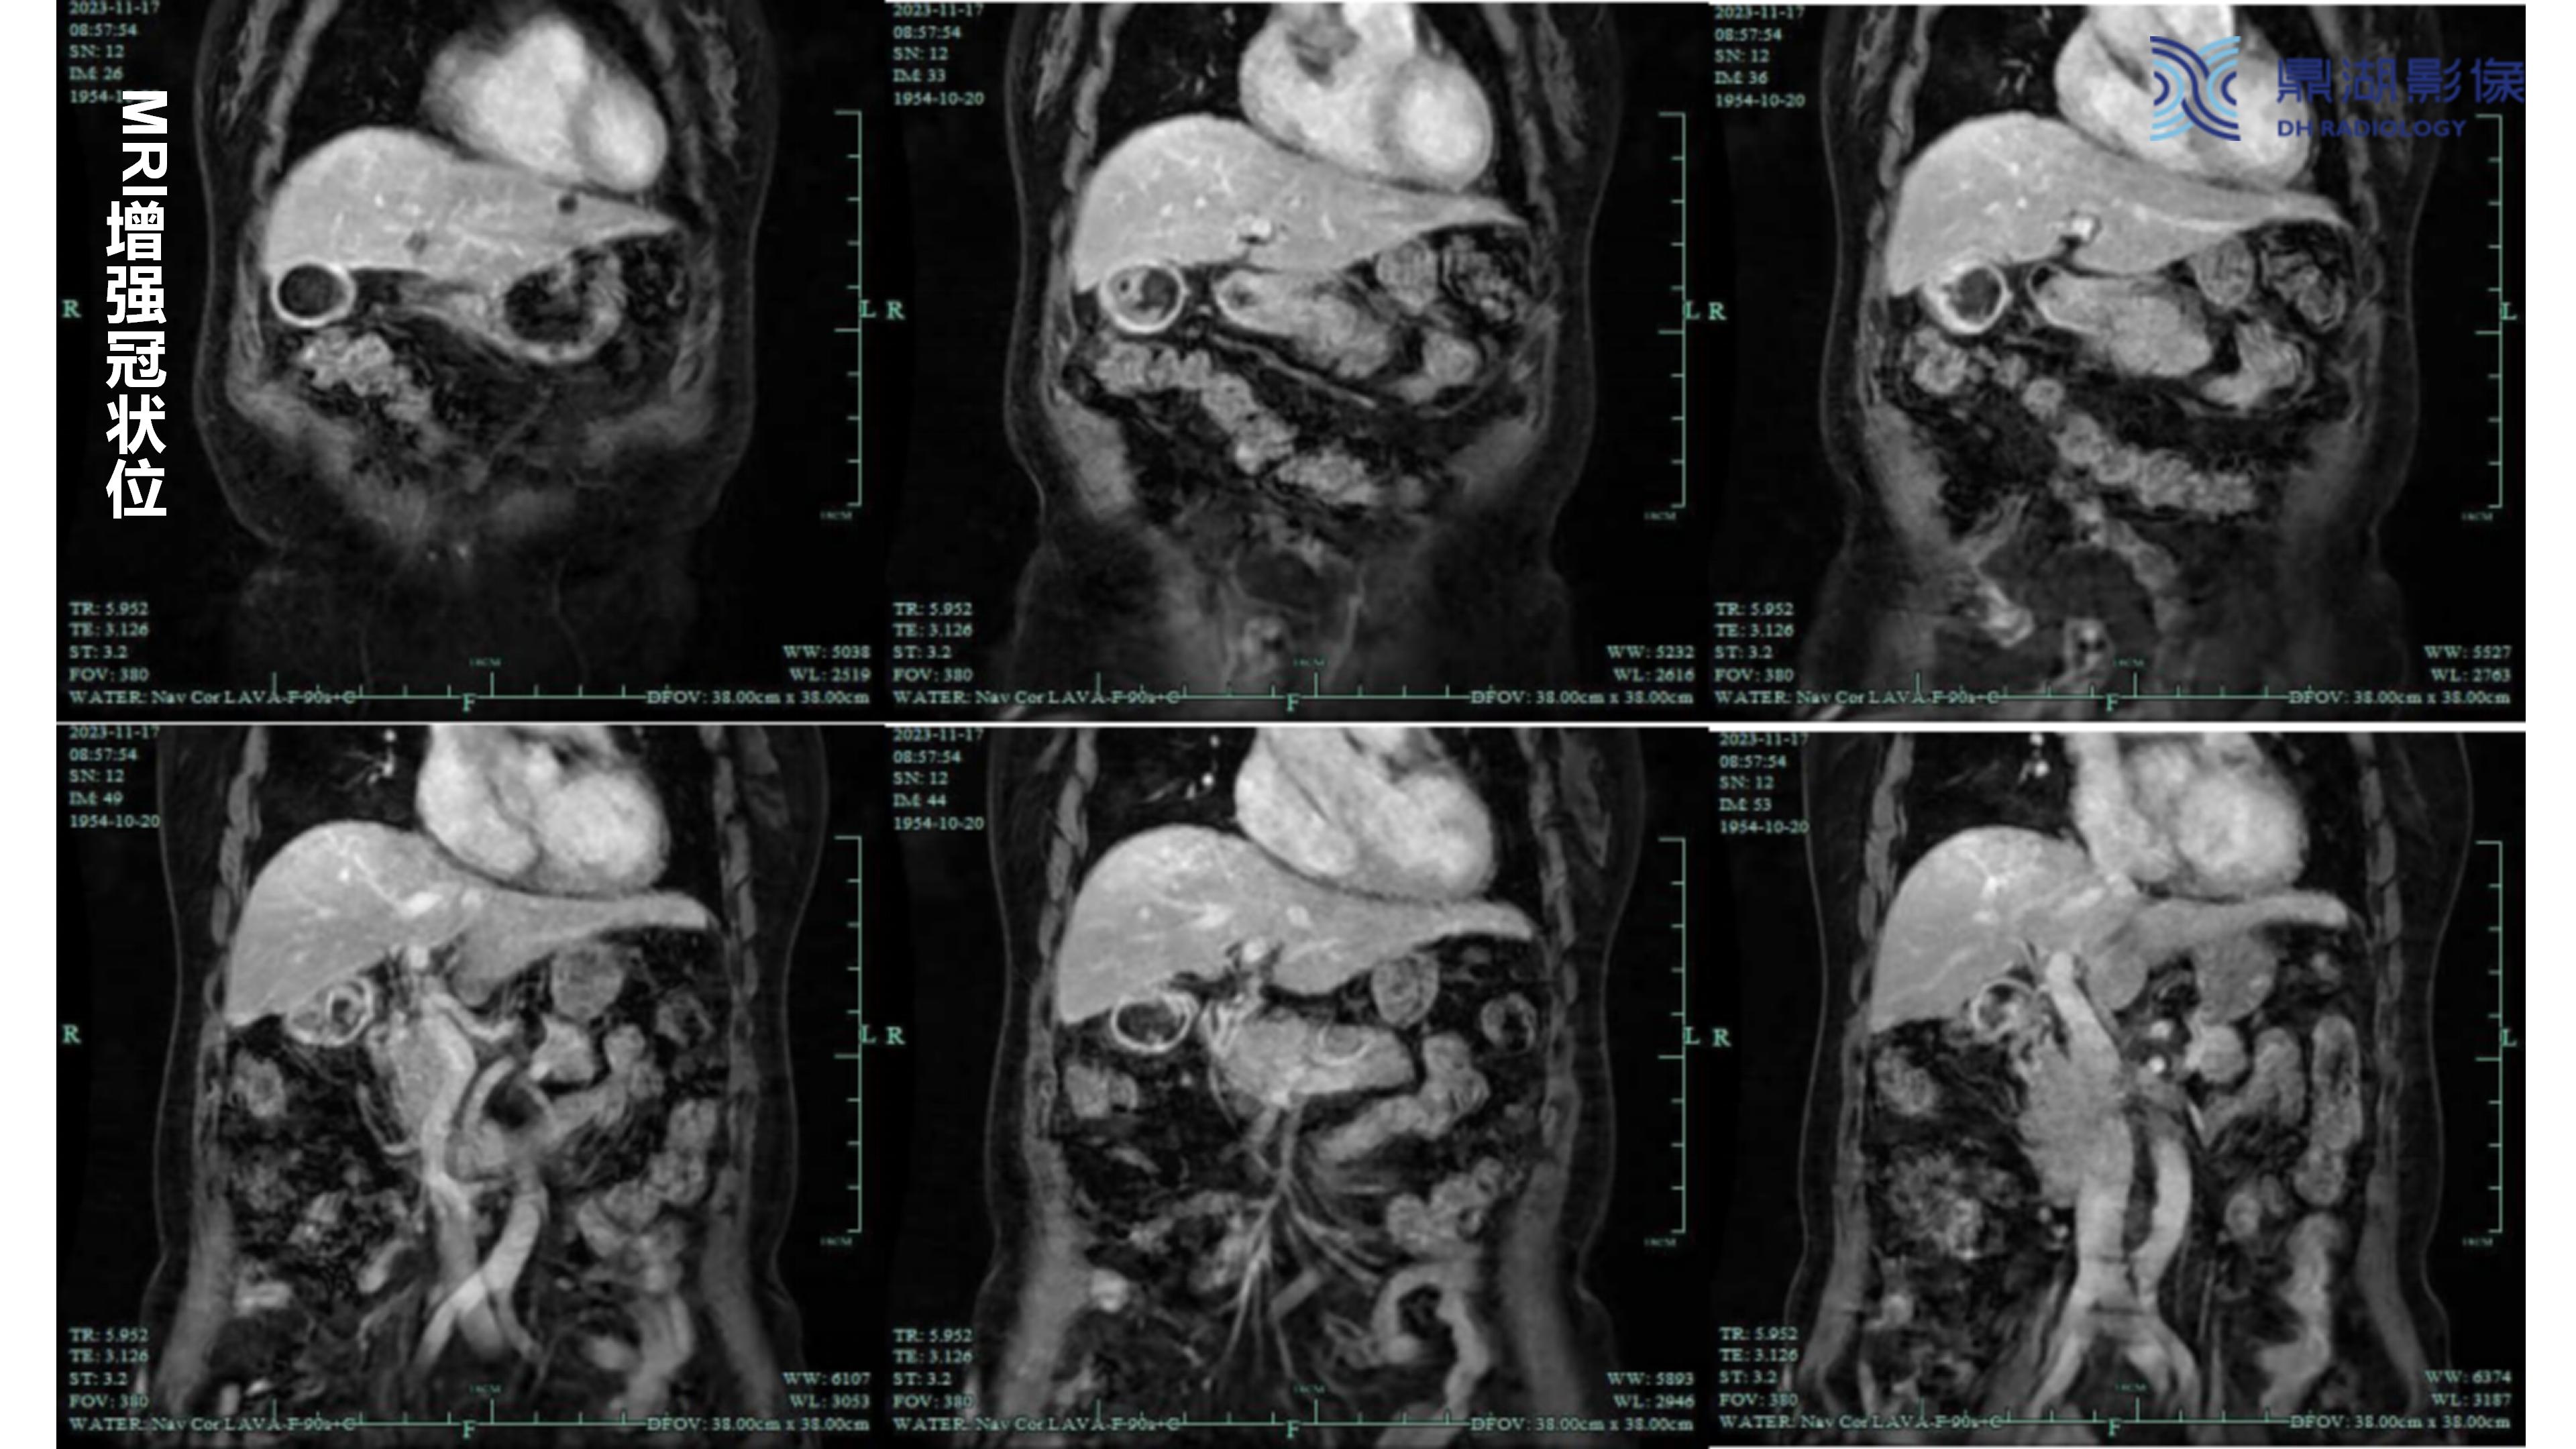

胆囊癌-鼎湖社群读片病例